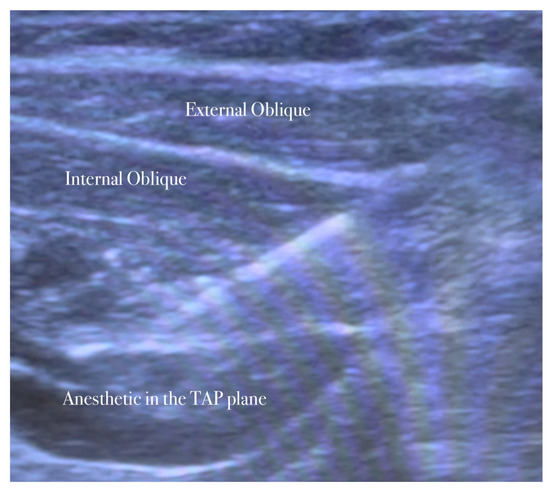

5.2. Ilioinguinal–Iliohypogastric Nerves Block

The patient lies in a supine position. The ilioinguinal–iliohypogastric nerves block is performed unilaterally using ultrasound guidance and placed in the transversus abdominis plane. Ilio-hypogastric and ilioinguinal nerves are the terminal branches of the anterior rami of the L1 spinal nerve. They emerge from the upper part of the lateral border of the psoas major muscle; both nerves cross obliquely anterior to the quadratus lumborum and iliacus muscles and perforate the transverse abdominis muscle near the anterior part of the iliac crest. In the anterior abdominal trunk, the nerves travel between the transverse abdominis and the internal oblique muscles [15].

A high-frequency, linear, high-resolution probe is initially kept perpendicularly on the lateral abdominal wall at the midaxillary line between the anterior superior iliac spine and the navel. In this place, the three abdominal muscles are seen below the subcutaneous fat and the plane between the internal oblique, and the transversus abdominis muscle is identified. The peritoneum can be seen as the fascia layer underneath the transversus abdominis muscle. Between the layers of the transversus abdominis and the internal oblique muscle, the splitting of the fascia layer is usually observed. It is on this plane where the ilioinguinal and iliohypogastric nerves pass through. Sometimes, both nerves pierce the internal oblique and appear between the internal and external oblique muscles.

The needle is inserted in the plane in a medial-to-lateral direction; 10 mL of anesthetic (Mepivacaine 10 mg/mL–Ropivacaine 7.5 mg/mL) is injected in the transversus abdominis plane, as seen in Figure 1, Figure 2, Figure 3 and Figure 4.

The needle is inserted through the three abdominal muscles in the transversus abdominis plane.

The anesthetic is injected in the transversus abdominis plane.